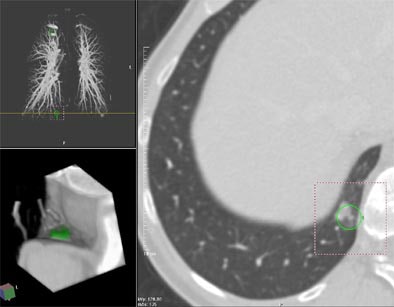

| Contrast enhanced spiral CT for routine follow-up in a 56-year-old woman with a history of breast cancer. Transaxial section at the level of the right phrenico-costal angle. A yellow line indicates the anatomical level of the displayed section within the volume data set in a coronal maximum intensity projection of the pulmonary vascular tree (left upper image panel). An 11-mm, part-solid slightly spiculated soft tissue lung lesion was missed at clinical interpretation but detected by CAD. 3-D volume rendering (left lower image panel) of the lesion highlighted in green displays the anatomic location of the lesion in the dorsal right phrenico-costal recess. Image courtesy of Dr. Joseph Schoepf. |